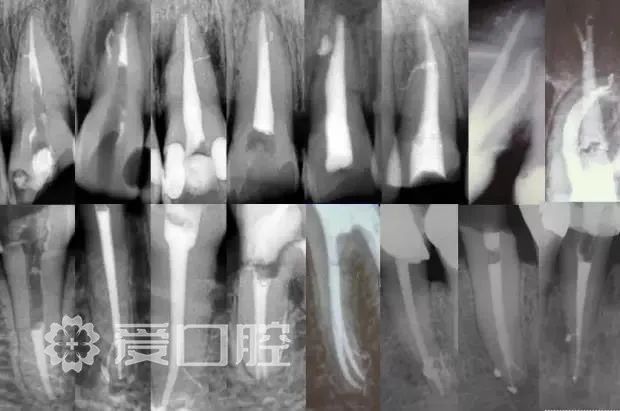

一个牙齿的根管治疗难易程度不单单是根管的弯曲、细小、牙位、是否再治疗决定的,开髓的直线进入和根管口的预先恰当处理可以简化很大的难度,开髓是根管成败的基础。

对于弯曲根管冠部的直线入口就显得尤为重要,冠部良好的直线入口可以避免侧穿、台阶、遗漏根管等问题的发生,冠部直线入口形成的良好情况,取决于医生的理念和合理的器械选择。开髓孔的大小不是由医生和患者的意愿决定的,而是由要治疗牙齿的髓腔大小决定的。

相信根管的数目比我们想象的多,根管系统的复杂程度比我们想象的见到的要更复杂,我们只有用尽所有努力和办法才可能达到预期目标。

对于上颌第一磨牙的MB2来说过去是偶尔有,现在是偶尔没有,各种文献报道的比例也不一致,在离体牙中几乎还没有见到没有的,临床中也是一样。对于寻找的方法来说,我觉得相信有才是最重要的,首先相信一定有就会想各种办法,找到的几率就会更多。如果有条件在显微镜和超声的配合下效率会更高。

根管预备理想的情况应该预备到多大锥度,多少号,预备后根管空间是金字塔还是埃菲尔铁塔。专家经过离体牙根尖切片研究发现根尖狭窄部远比想象的要大,如果根管预备太小就会残留感染物,根管的部分空间就不会预备到,残留的感染物就会造成治疗效果达不到预期目标。只有做到了充分的预备,尽可能的多冲洗才会有好的结果。

根管治疗要做到看清楚,去干净,充恰满,封严密,就会达到期望的结果。2200年前的病例只充填了冠1/3可以理解、可以接受;今天我们有先进的设备和材料,就要充填出大锥度高密度的完美结果。理念决定技术,标准决定技术的提高和进步。